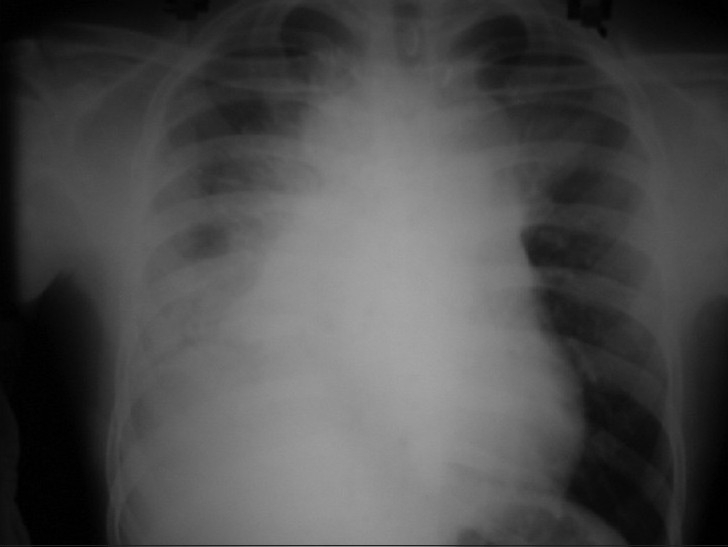

An 18-year-old male patient presented in September 2006 with dull retrosternal and right-sided chest pain, dyspnea and dysphagia for solids of 1-month duration. Chest X-ray showed lobulated homogenous opacity occupying the right mid-zone and lower zone [Figure 1]. There was no calcification.

| Figure 1 Chest X ray PA view (2006) shows homogenous opacity in right mid and lower zone